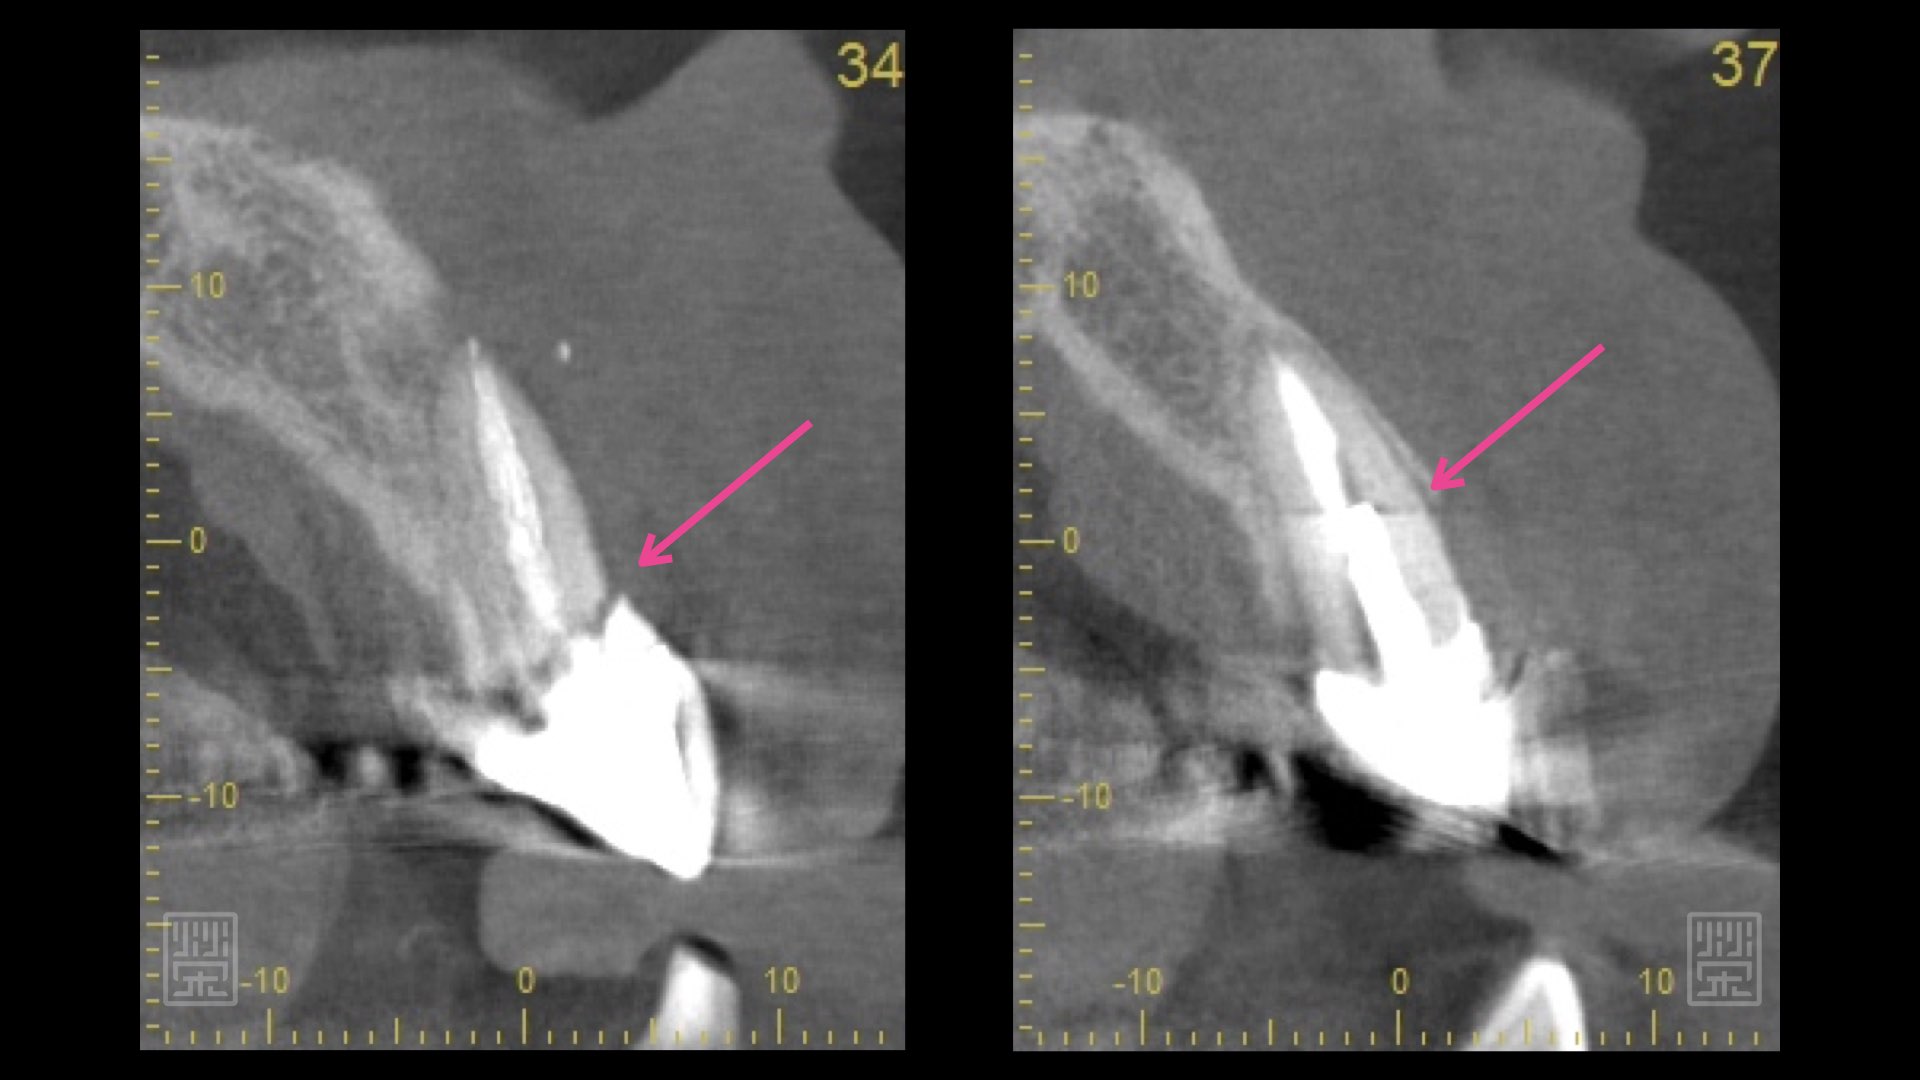

X光片明顯看到中門牙斷裂痕

斷層掃描發現中門牙與側門牙都有斷裂痕